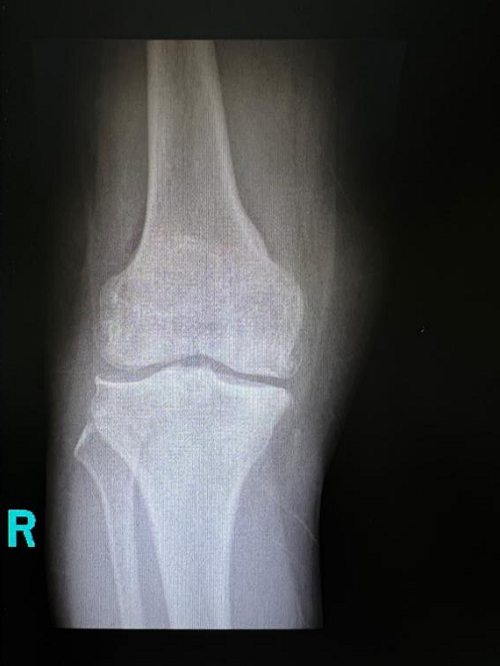

在我院骨科病区,62岁的袭奶奶就享受到了新政策带来的实惠。袭奶奶一直饱受膝关节炎的折磨,膝关节反复疼痛,行走十分困难。她接受了长期的保守治疗,但疗效很差,所以人工膝关节置换是她最后的救命稻草。但苦于人工膝关节价格昂贵,一直没有下定决心接受手术。

袭奶奶一听说人工关节大幅降价后,第一时间就找到骨科贾育松主任,接受了人工全膝关节置换手术。手术效果很好,恢复很快,第二天就在助行器的辅助下站立活动。出院两周后来门诊复查时,走路已完全不需要任何辅助,她表示对治疗效果非常满意,还说赶上了国家的好政策,既治好了病,也节省了治疗费用。